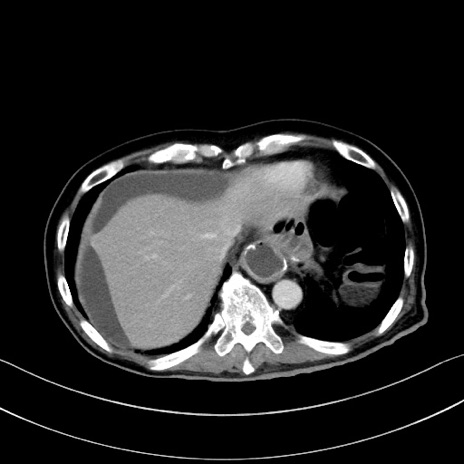

症例28(横断像)

【症例】60歳代男性

【主訴】嘔吐

【現病歴】胃癌にて胃全摘後。食思不振が悪化し、夜中に嘔吐することがある。

【既往歴】胃癌、胃全摘、脾摘、胆摘後

【データ】WBC 5900、CRP 10.56